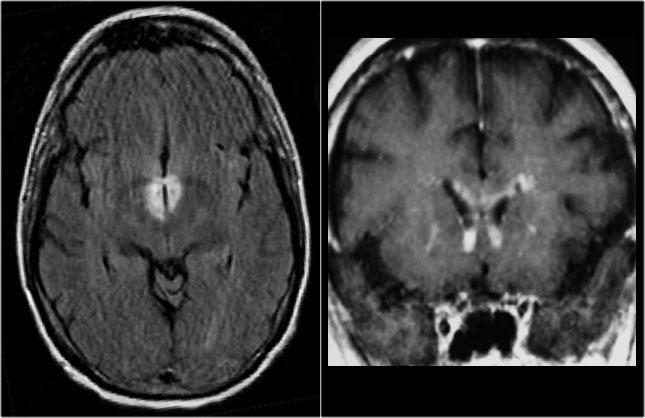

Bệnh Xơ Cứng Rải Rác

MS: tổn thương khu trú đoạn ngắn hình nêm ở cột sau tủy sống kèm theo các tổn thương chất trắng quanh não thất điển hình.

Khi phát hiện tổn thương ở tủy sống, việc chụp thêm não cũng rất hữu ích.

MRI não cho thấy các tổn thương quanh não thất và một tổn thương ở thể chai.

Các vị trí này rất đặc trưng cho MS.

Ở một bệnh nhân khác có các tổn thương không đặc hiệu trong tủy sống.

Chỉ dựa vào khảo sát cột sống đơn thuần, chúng ta có một chẩn đoán phân biệt rộng.

Tuy nhiên khi khảo sát thêm não, sẽ rõ ràng rằng chúng ta đang đối mặt với MS.

Tiếp tục xem các hình ảnh của não.

Trong trường hợp này, các hình ảnh trên não rất hữu ích.

Vị trí của các tổn thương rất điển hình: cầu não, quanh não thất và dưới vỏ não.